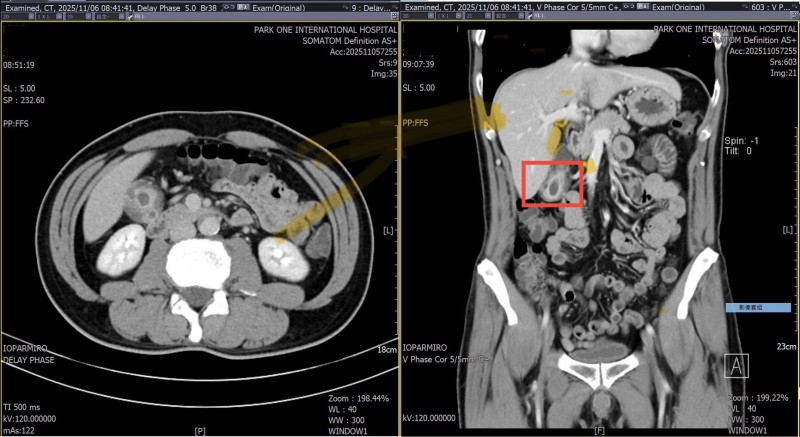

多年腹痛難解竟是膽囊腺肌症 影像易被誤診膽結石

高雄49歲的林姓男子五年來,因心窩悶痛與右上腹脹痛四處求醫,做過胃鏡與多次超音波,皆僅顯示輕微胃炎或無結石異常,卻反覆發作的疼痛,長期困擾卻始終找不到病因,轉診博田國際醫...…